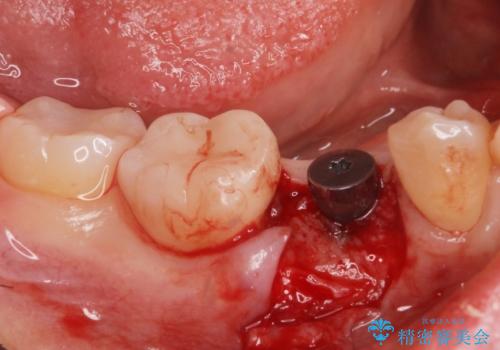

インプラント治療

- 過去に抜けてしまった歯のところにインプラントを入れたいとの事で来院。

CTで確認したところ骨の高さや厚みがインプラント埋入できる状態でしたのでインプラント治療を行いました。